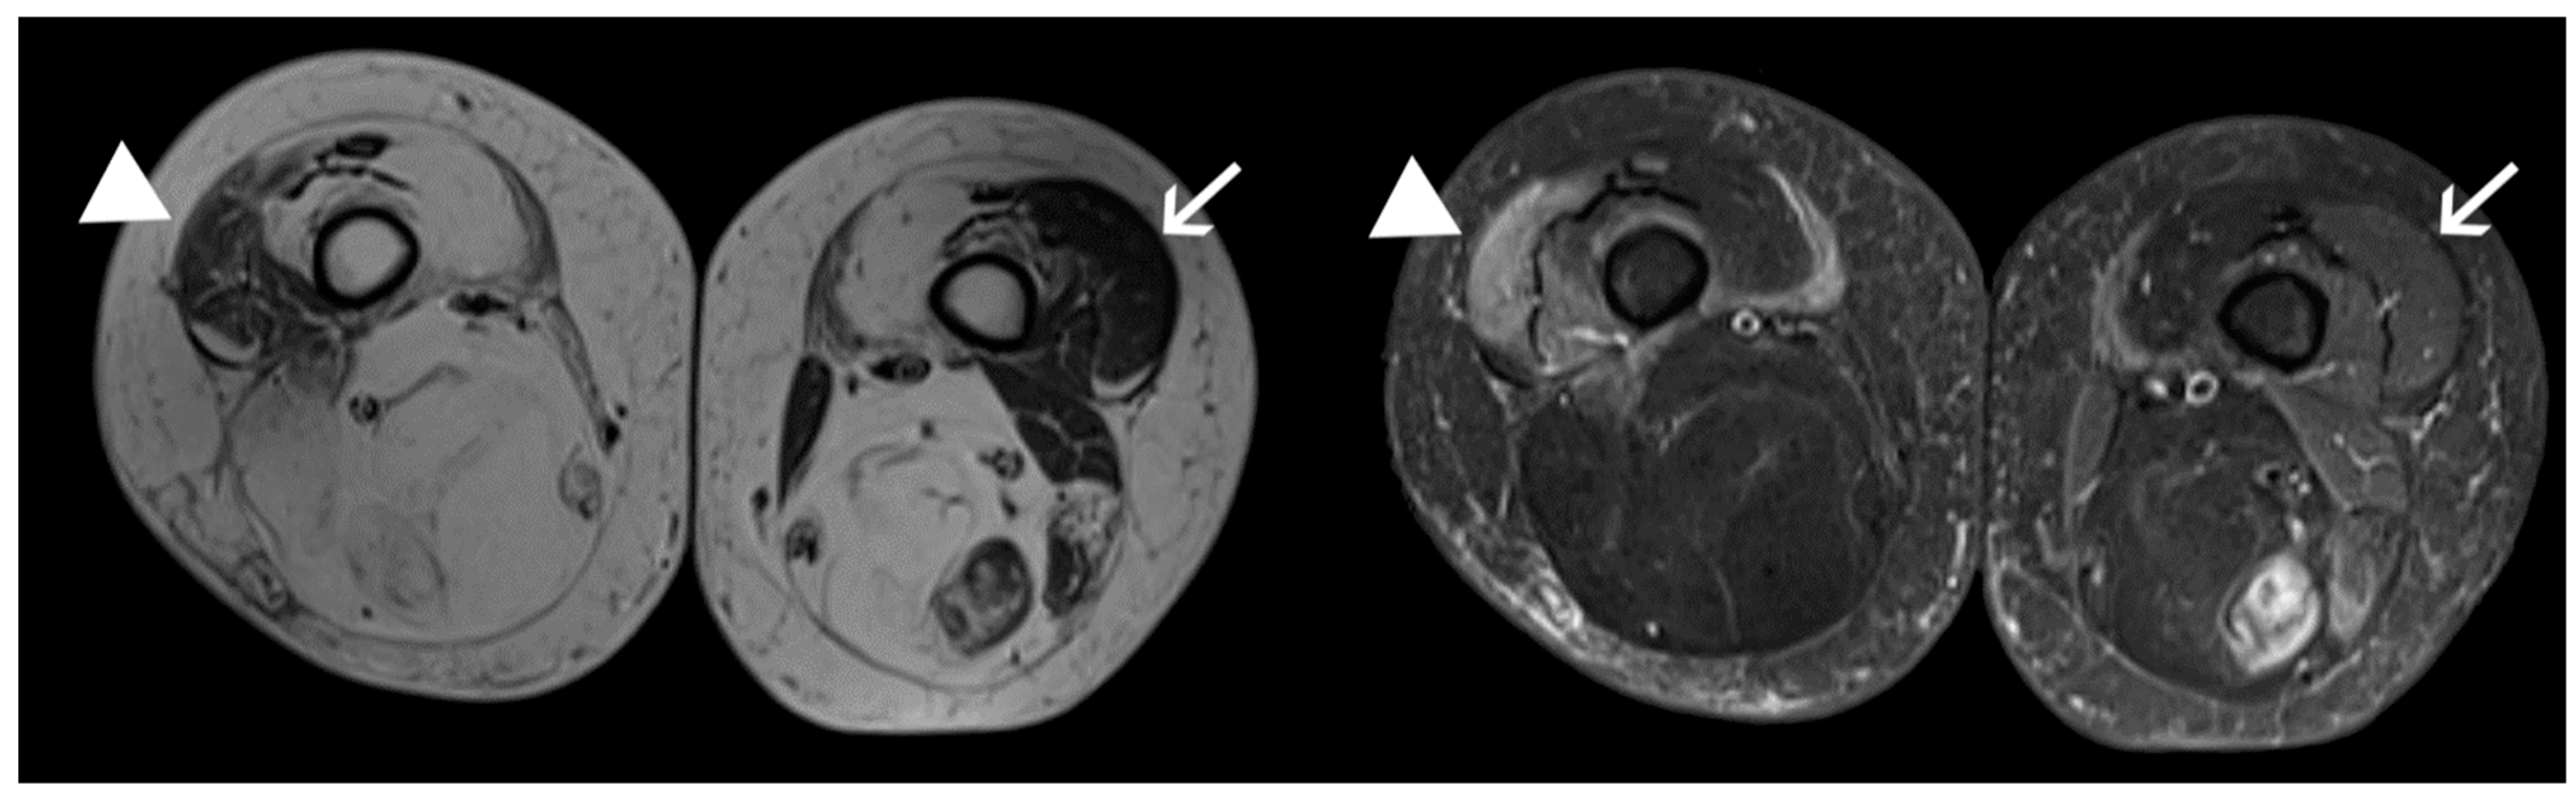

:1. Introduction

4.1. Patients and Samples